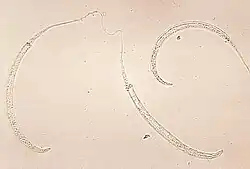

Photomicrograph of larvae